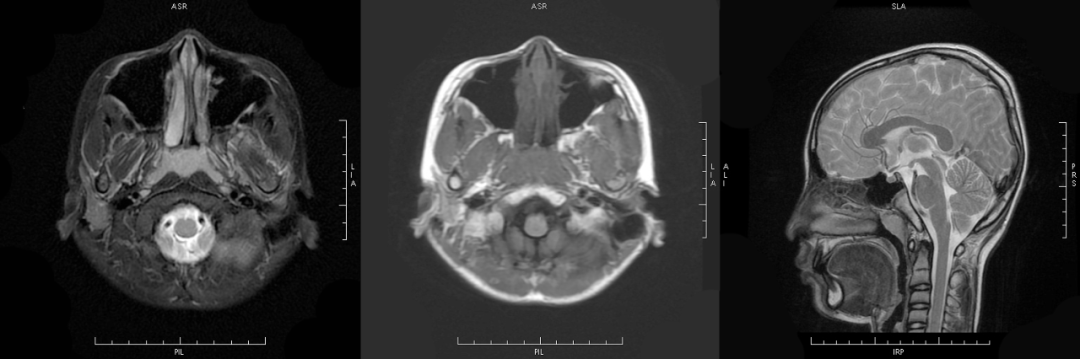

MRI 表现:鼻咽后壁及两侧壁不规则软组织肿块,信号多较均匀,T1WI 像呈等信号,T2WI 像呈稍高信号,DWI 像为明显高信号。增强扫描肿块常轻-中度均匀强化,液化坏死少见。颈部淋巴结肿大常见。肿大淋巴结多边缘规则,内部密度或信号均匀,增强扫描轻度强化。对邻近组织侵犯少,肿块与咽后壁头长肌等分界清楚,多无颅底及相邻骨质破坏。鼻咽部肿块虽较明显,但咽旁间隙较清晰,或只有受压改变。

MRI 表现:早期表现为鼻咽顶后壁轻度软组织增厚、突起,表面不规则、边界不清;咽隐窝变浅甚至消失,鼻咽轮廓改变,双侧结构不对称;进展期肿瘤增大向周围组织、结构浸润生长,并可破坏颅底骨质结构,以中线部蝶骨体和枕骨斜坡最常见。肿瘤在 T1WI 像上呈中等或中低信号,T2WI 像上呈中等或中高信号,边缘模糊呈浸润状;增强扫描多呈明显强化,肿块内坏死区无强化。颈部较小的转移淋巴结边缘多较清楚、信号均匀;较大的淋巴结中央常见液化坏死,多发增大的淋巴结可融合呈巨大的肿块,信号不均匀。

③MRI 表现为鼻咽顶后部软组织弥漫增厚,通常双侧对称,边界清楚,位于粘膜浅表、咽颅底筋膜的内侧,不累及深层结构,基膜完整,头长肌完好;T1WI 呈中等信号,T2WI 呈均匀中高信号,与正常淋巴组织相同,增强呈中等强化。

MRI 表现:肿瘤与周围组织分界清楚,信号改变类似血供丰富的血管瘤,T1WI 呈中低信号,T2WI 呈中高信号,纤维组织丰富区呈低信号,因此多呈高低混杂信号,多数肿块内可见流空血管影。增强扫描多呈显著不均匀强化。